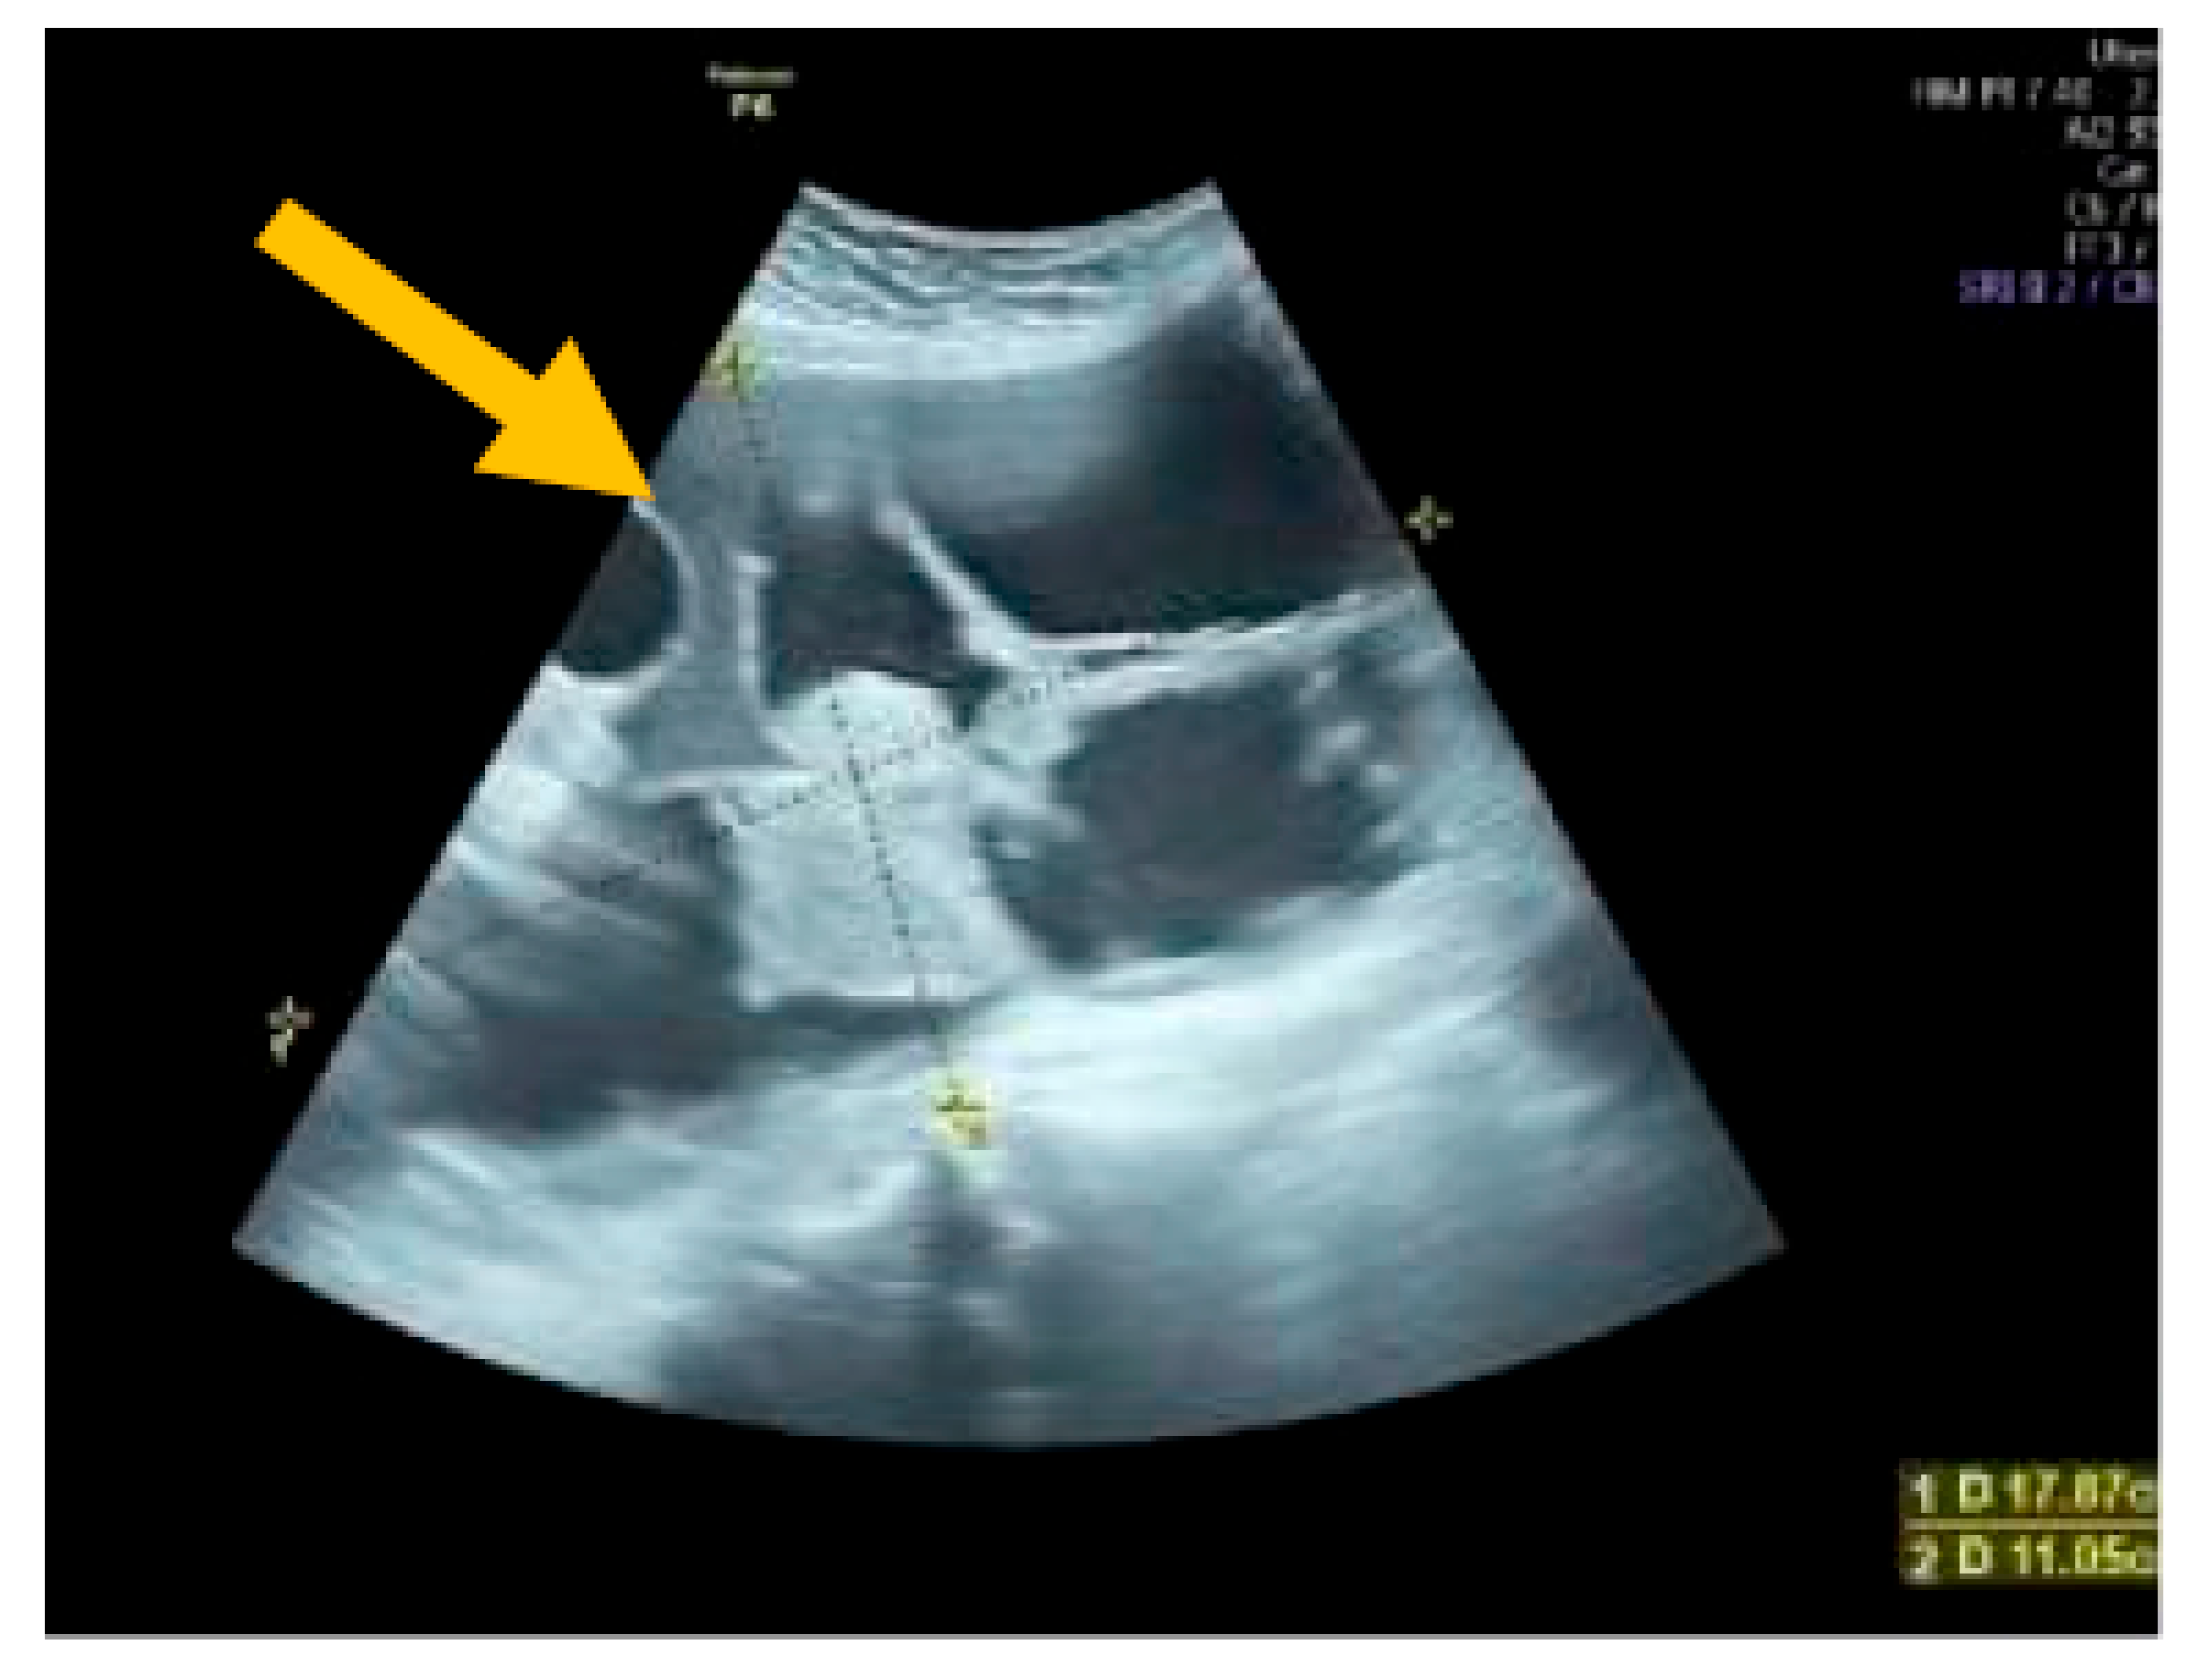

The existence of irregular solid tumors, ascites, at least four papillary structures, an irregular multilocular-solid tumor (diameter at least 10 cm), and very strong blood flow on a color Doppler assessment are malignant indicators, whereas a unilocular cyst, the presence of solid components (max diameter < 7 mm), the presence of an acoustic shadow, a smooth multilocular tumor (max diameter < 10 cm), and the absence of detectable blood flow on the Doppler predispose for the presence of a benign mass [24] (Figure 1, Figure 2 and Figure 3).

Figure 2.

Multilocular solid tumor. (Yellow arrow indicates the presence of a cyst with multiple septums, measurable solid components, and papillary projections.)